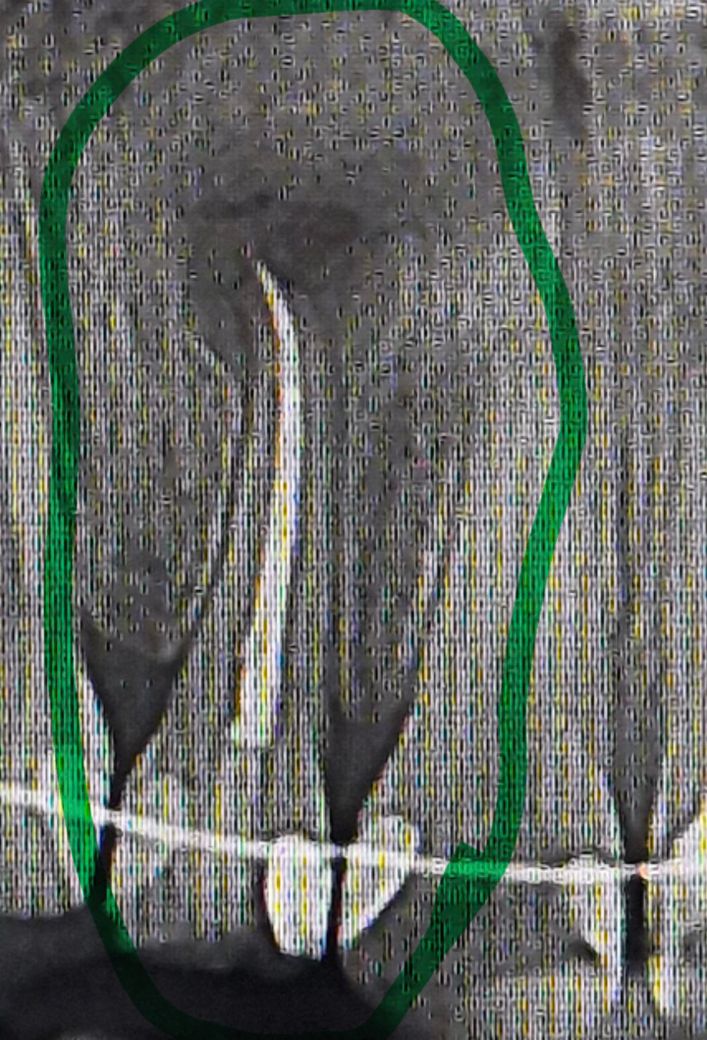

1년 전쯤 앞니쪽 치아에 뿌리염증이 크게 생겨서 신경치료를 했는데 최근에 교정 치과가서 엑스레이를 찍어보니까 의사쌤이 뿌리염증이 생겼다고 하시더라구요.. 엑스레이가 백퍼센트 완벽한게 아니라 뿌리염증이 아닐수도 있으니 나중에 통증 느껴지면 신경치료했던 치과를 다시 가보라는데 혹시 사진에 있는게 뿌리염증이 재발한게 맞나요..? 맞다면 심한편인지 아닌지 굼궁금합니다..

• 1번 째 사진

x-ray에서 치아뿌리끝에 확실한 염증 보입니다. 이런경우 치아뿌리끝을 잘라내는 치근단절제술 해야 합니다.

원래 어떤 상태엿는지 모르겟지만 치아 뿌리끝에 염증이 잇는거 같습니다. 다시 치료를 하시는게 좋을것같습니다.

사진에 있는게 뿌리염증이 재발한게 맞아 보이지만 간혹 회복이 되었을 떄에도 저렇게 남기도합니다.

1. 비포,애프터 사진이 없으니 재발한 것인지는 모릅니다

2. 현 상태만 보자면 치아 뿌리끝으로 잇몸뼈에 염증이 만성적으로 있는 상태는 맞습니다.

사진으로 봤을 경우에는 치근단 질환이 생긴것이 맞는것으로 보입니다.

치근단 질환이 생겼을 경우에는 감염의 원인이 되는 부위를 치료하는것이 좋으며 뿌리에 금이갔을 경우 발치를 해야 하는경우도 있습니다.